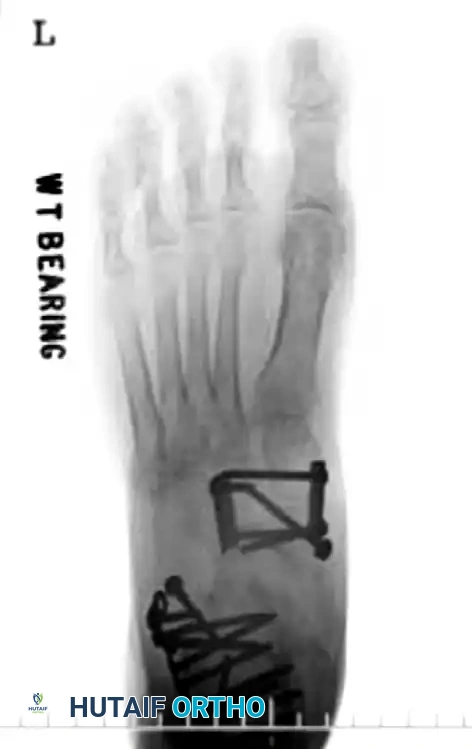

Clinical Evaluation and Radiographic Parameters

Any injury resulting in midfoot tenderness, swelling, or an inability to bear weight merits rigorous evaluation.

Radiographic Evaluation:

Standard non-weight-bearing radiographs often miss subtle instability. Weight-bearing radiographs are absolute requirements if the patient can tolerate them. If the patient cannot bear weight, a short-leg cast should be applied for 10-14 days, followed by repeat weight-bearing films.

Key radiographic parameters to evaluate:

1. The medial shaft of the 2nd metatarsal must align perfectly with the medial aspect of the middle cuneiform on the AP view.

2. The medial shaft of the 4th metatarsal must align perfectly with the medial aspect of the cuboid on the oblique view.

3. The 1st metatarsal-cuneiform articulation must show no incongruency.

4. The "Fleck Sign": Look for a small bony avulsion in the space between the medial cuneiform and the base of the 2nd metatarsal. This represents a bony avulsion of the Lisfranc ligament.

5. Evaluate the naviculocuneiform articulation for subtle subluxation.